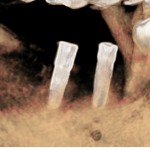

術後 埋入後